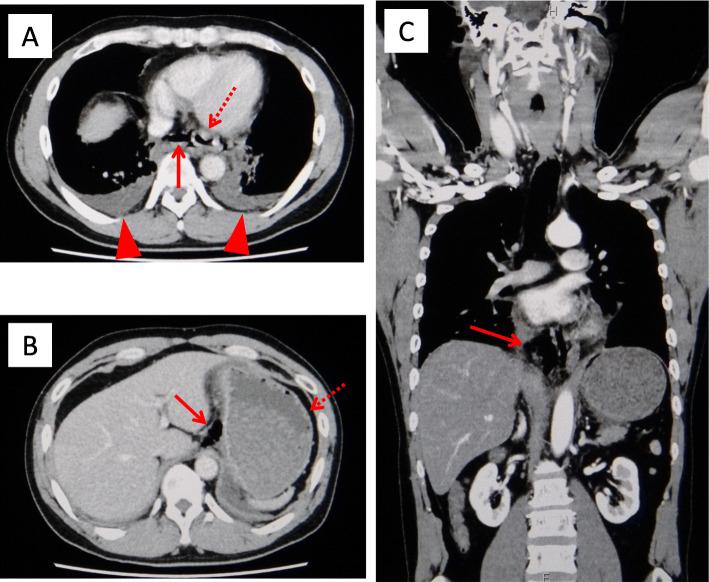

The patient in case 1 complained of severe chest pain and nausea and vomited on arrival at the hospital. He was subsequently diagnosed with Boerhaave syndrome coupled with mediastinitis using computed tomography (CT) and esophagogram. An emergency operation was successfully performed, in which a 3-cm tear was found on the left posterior wall of the distal esophagus. The patient subsequently had anastomotic leakage but was discharged 41 days later. The patient in case 2 complained of severe chest pain, nausea, vomiting, and hematemesis on arrival. He was suggested of having Boerhaave syndrome without mediastinitis on CT. The symptoms gradually disappeared after conservative treatment. Upper gastrointestinal endoscopy performed on the ninth day revealed a scar on the left wall of the distal esophagus. The patient was discharged 11 days later. In addition to the varying severity between the cases, the patient in case 2 was initially considered to have Mallory-Weiss syndrome.

病例1中的患者在入院时主诉严重胸痛、恶心并呕吐。随后通过计算机断层扫描(CT)和食管造影被诊断为Boerhaave综合征合并纵隔炎。成功进行了急诊手术,术中发现食管远端后壁有一处3厘米的撕裂口。该患者随后出现吻合口漏,但在41天后出院。病例2中的患者在入院时主诉严重胸痛、恶心、呕吐和呕血。CT检查提示其患有Boerhaave综合征但无纵隔炎。保守治疗后症状逐渐消失。在第9天进行的上消化道内镜检查显示食管远端左壁有一处瘢痕。该患者在11天后出院。除了病例之间严重程度不同外,病例2中的患者最初被认为患有马洛里-魏斯综合征。